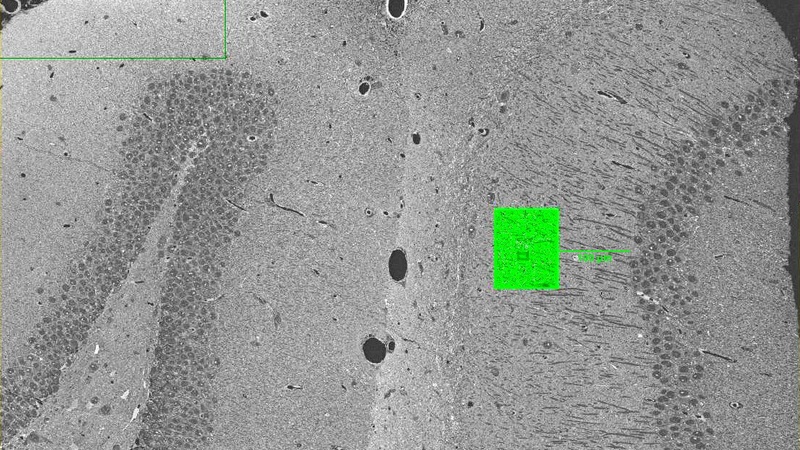

In SEM blockface imaging, it is quick and simple to produce overviews of large tissue sections (see below). Then, a much smaller, specific area can be localized and imaged at higher magnification to study morphology and/or to quantify features using a stereology approach.

Hannah Somerfield/Dr Adrian Butcher, Professor Giovanna Mallucci’s Group, UK Dementia Research Institute, University of Cambridge – Quantification of synapses in a mouse model of neurodegeneration

High resolution map of the synaptic region of the hippocampus. The area in the green square is shown below in more detail.